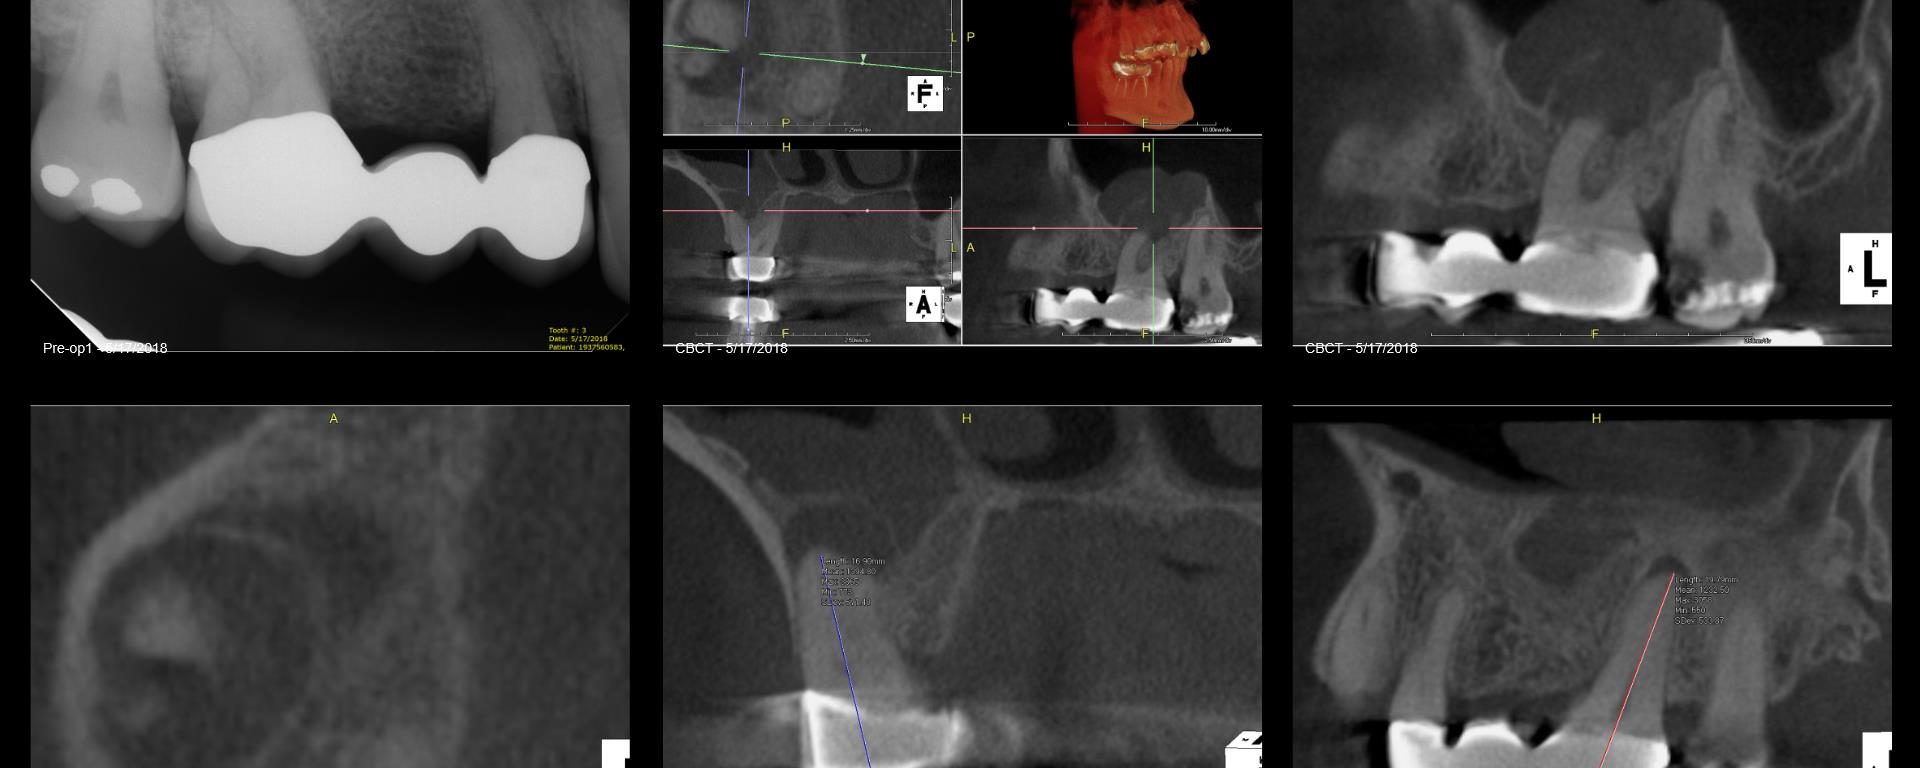

Morning consult. Never any symptoms. I’m thinking maybe X-Nav on this one? gbc